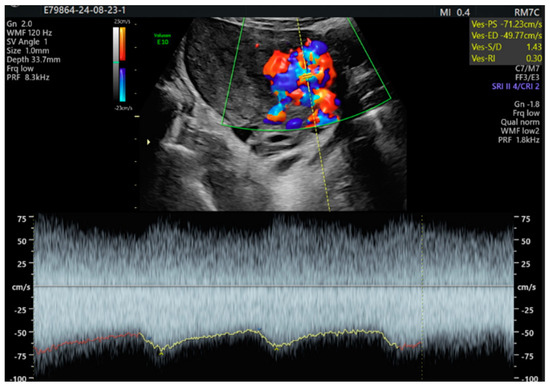

2. Case Presentation